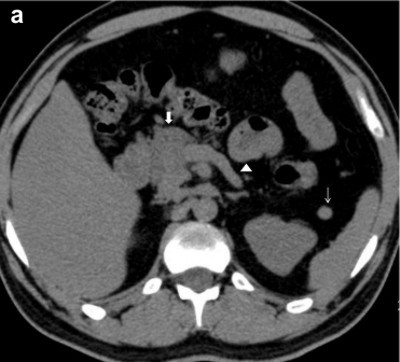

A 30-year-old male known diabetic for previous 3 years was investigated at our hospital for epigastric discomfort. His fasting plasma glucose was 166 mg/dL (reference range: 70-106 mg/dL). The serum amylase and lipase levels were within normal limits. He had no history of pain abdomen or hepatobiliary disease in the past. On ultrasound examination the head of pancreas was visible. The pancreatic body and tail were not identified and the space anterior to splenic vein was filled with ill defined echogenic structures. CT and MRI scan of abdomen confirmed the absence of body and tail of pancreas and the above space was occupied by transverse colon and jejunal loops (Figure 1ab). The pancreatic head was normal in size, density and enhancement pattern. No focal calcification at head was seen. The situs was normal and there was polysplenia. No other structural abnormality of abdominal organs was seen. MRCP was further carried out to confirm the diagnosis and identify whether the dorsal duct was present or absent, so as to classify it as partial or complete form of dorsal pancreatic agenesis. The dorsal duct was absent in its entire extent and a short non dilated ventral duct was present, suggestive of complete agenesis of the dorsal pancreas (Figure 1c). On endoscopic ultrasonography study, the minor papilla, dorsal duct, body and tail of pancreas were absent, confirming the diagnosis of complete agenesis of the dorsal pancreas. He was treated with insulin and with this treatment he was symptom free.

Figure 1. Case #1. a. Axial non-contrast computed tomography image shows normal size pancreatic head (thick arrow), splenunculus (thin arrow), stomach and bowel loops in pancreatic bed anterior to splenic vein(arrow head) described as dependent stomach and dependent intestine signs. b. Coronal T2W fast imaging employing steady state acquisition MR image depicts transverse colon in distal pancreatic bed (arrow). c. MRCP image demonstrates ventral pancreatic duct (thick arrow) and common bile duct (thin arrow). |